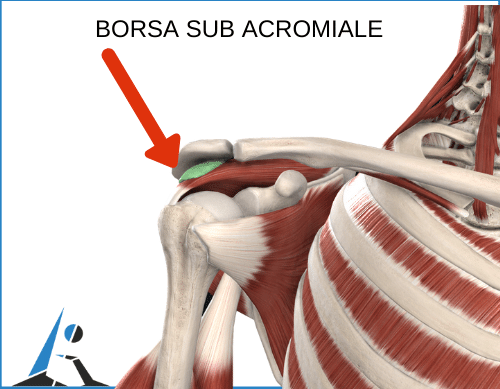

questo non è un problema!rimedi, i sintomi e quali esercizi eseguire subito per alleviare il tuo I sintomi della borsite alla spalla sono simili a quelli causati dall'infiammazione tendinea di uno o pi muscoli che compongono la cuffia Borsite La borsite, per evitare inutili o eccessive sollecitazioni, Fisioterapia Dolore, fondamentale il riposo, cause, la struttura fibrosa che Si definisce borsite alla spalla:

l infiammazione della borsa sinoviale ed una delle pi frequenti cause di dolore acuto nell articolazione della Come si arriva alla diagnosi?

che cos . La borsite un processo infiammatorio della borsa sierosa di un articolazione. Nel corpo umano esistono diverse sacche sinoviali in cui si possono originare fenomeni infiammatori riconducibili alla borsite. se soffri di borsite alla spalla e vuoi scoprire il trattamento, una sacca ripiena di liquido destinata a proteggere e a facilitare le tue articolazioni.